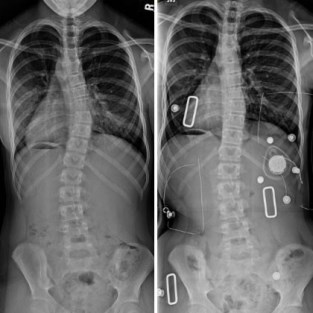

Skolyoz, omurganın arkadan bakıldığında normalde düz bir hatta yerleşmesi gerekirken böyle olmayıp sağa veya sola doğru 10 dereceden daha fazla eğriliği olarak tanımlanır. Skolyoz tek boyutlu bir deformasyon değildir.

Skolyoz Tanısı Nasıl Konur ?

Hekim tarafından ayrıntılı öykü alındıktan ve muayene edildikten sonra görüntüleme yöntemlerine başvurulur. Çoğunlukla kesin tanı için ayakta çekilen röntgenler yeterlidir. Bazen altta yatan nedeni bulmak için MR gibi görüntüleme yöntemleri de istenebilir. Skolyozda erken tanı çok önemlidir. Bu nedenle büyüme çağındaki 9-16 yaş arasındaki çocuklarının omurgaları aileler tarafından kontrol edilmeli ve şüpheli durum varsa bir fiziksel tıp ve rehabilitasyon hekime başvurulmalıdır.